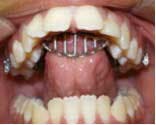

Prolonged thumb-sucking turns into a habit that can cause a dental and even a skeletal open bite. If the habit ceases while the child is still growing, the dental open bite can self-correct, but sometimes the help of a dentist or an orthodontist is required to correct the position of the teeth and align the jaws. Oftentimes the actual thumb-sucking may stop, but the child develops a tongue-thrusting habit while eating, speaking, and swallowing. This tongue-thrusting then perpetuates the deleterious force on the dentition and jaws. If the open bite is not corrected while the child is growing, then jaw surgery may be required to correct the bite.